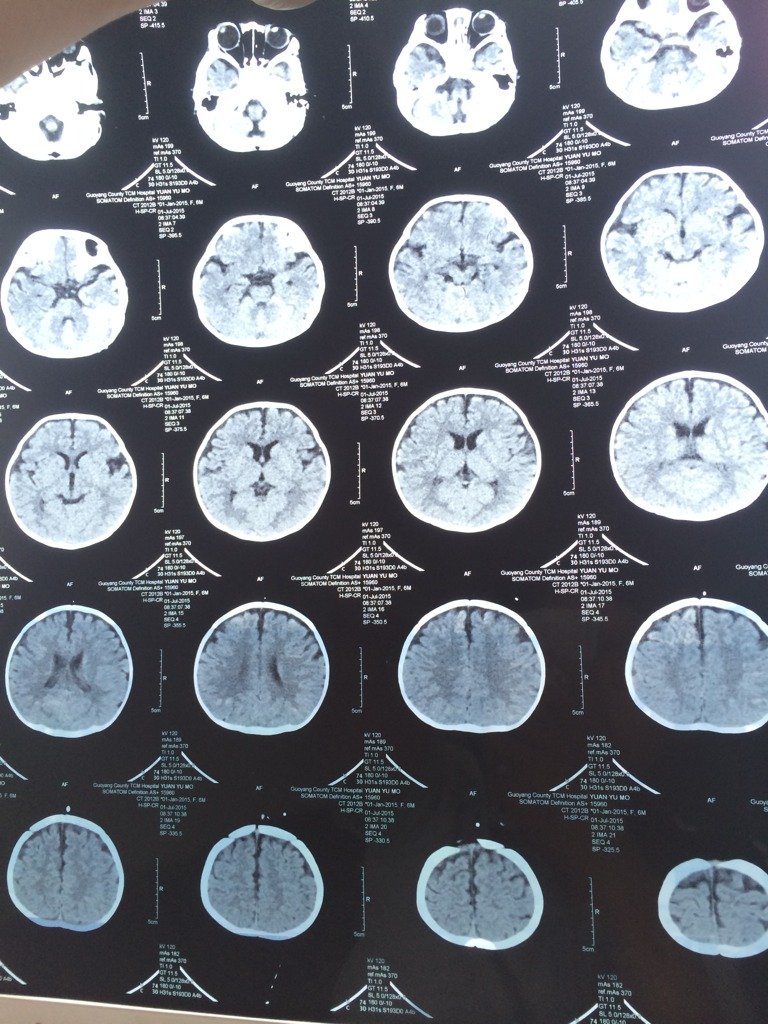

有神经外科的权威专家吗?这张CT图有脑积水吗?有的医生说是有的说不是,到底是不是

这个不好说看患者岁数的,如果是老人的话,没有,如果是年轻人的话有一点的,不过不是很严重,在观察一段时间看看吧。有症状对证处理就可以了。